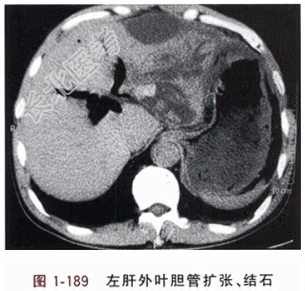

- [材料题] 患者,男,52岁。反复右上腹痛、畏寒、发热30年,复发加重全腹痛8d。近30年,反复右上腹痛、畏寒、发热,无黄疸,曾诊为“肝胆管结石”,经当地医院输液、抗生素等处理,症状缓解。8d前症状复发,并感全腹痛、腹胀,再度住入某医院,经抗生素、输液治疗8d,症状无缓解,并认为无法手术治疗,应继续非手术治疗。由于腹痛难忍,而要求转来我院。T37.8℃,P98次/分,R22次/分,BP15/10.9kPa(112/82mmHg)。皮肤、巩膜未见黄染。心律齐,双肺呼吸音清。腹胀满,未见浅静脉曲张,无胃肠型,全腹肌紧张,压痛、反跳痛以剑突右下方及左上腹为显。肝、胆囊及脾未触及,右肝浊音界存在,叩击右肝区示心窝部疼痛。腹水征存在。双腰背部无抬举痛。WBC23.95×10⁹/L,N0.92,PLT124×10⁹/L,TP48.8g/L,ALB26.7g/L,TBIL13.5μmol/L,DBIL5.6μmol/L,PA63mg/L,CHE2393.3U/L。CT:右肝轮廓清。左肝外叶胆管呈囊状扩张,其内胆石存在,囊状胆管似穿破于左膈下,局部形成液体积聚区域。右肝内胆管未见胆石(图1-189)。胆囊显示不清。肝内外胆管大量积气。右上腹肠管扩张、胀气。腹膜腔内积液。